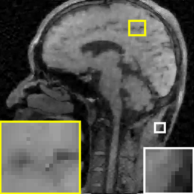

Recent works applied learned unions of transforms to other applications. For example, the union of transforms model was pre-learned (from a dataset) and used in a clustering-based low-dose 3D CT reconstruction scheme [26]. Fig. 4 shows an example of high quality reconstructions obtained with this scheme. While the work used a PWLS-type reconstruction cost, a more recent method [132] replaced the weighted least squares data-fidelity term with the shifted-Poisson likelihood penalty, which further improved image quality and reduced bias in the reconstruction in ultra low-dose settings. Other recent works combined learned union of transforms models with material image models and applied it to image-domain material decomposition in dual-energy CT with high quality results [137, 138].

In [157], the neural networks were designed to learn the relationship between contourlet transform coefficients of the low-dose input and high dose label data. Later, this problem is formally extended to wavelet domain residual network (WavResNet) to improve the performance [159] (see Fig. 8 for an example). Here, the choice of appropriate transform domain facilitating efficient learning is important and usually based on domain expertise. For example, in a recent deep neural network architecture for interior tomography problems, [201] observed that the neural network is more robust with respect to different ROI sizes, detector pitch, short scan and sparse view artifacts, if the neural network is designed in the differentiated backprojection (DBP) domain. The DBP is well-known in the CT community for its robustness to short scan artifact, interior tomography, etc, which clearly shows the importance of domain expertise in designing neural networks.